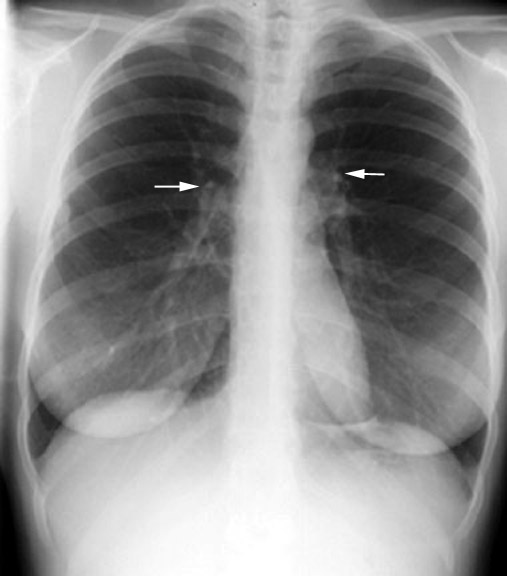

Hilum The left hilum is slightly at a higher level compared to right hilum. The hilum can be pulled up or down by lobar atelectasis. Alteration of the normal relationship between right and left hilum is a helpful clue for determining which lobe has lost the volume. |